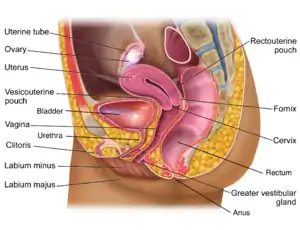

The human vagina is an elastic, muscular canal that extends from the vulva to the cervix.[9][10] The opening of the vagina lies in the urogenital triangle. The urogenital triangle is the front triangle of the perineum and also consists of the urethral opening and associated parts of the external genitalia.[11] The vaginal canal travels upwards and backwards, between the urethra at the front, and the rectum at the back. Near the upper vagina, the cervix protrudes into the vagina on its front surface at approximately a 90 degree angle.[12] The vaginal and urethral openings are protected by the labia.[13]

When not sexually aroused, the vagina is a collapsed tube, with the front and back walls placed together. The lateral walls, especially their middle area, are relatively more rigid. Because of this, the collapsed vagina has an H-shaped cross section.[10][14] Behind, the upper vagina is separated from the rectum by the recto-uterine pouch, the middle vagina by loose connective tissue, and the lower vagina by the perineal body.[15] Where the vaginal lumen surrounds the cervix of the uterus, it is divided into four continuous regions (vaginal fornices); these are the anterior, posterior, right lateral, and left lateral fornices.[9][10] The posterior fornix is deeper than the anterior fornix.[10]